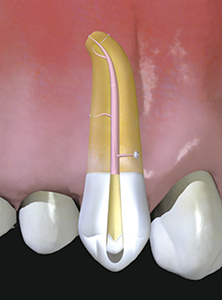

Inside the root of the tooth, there is a cavity called a "root canal" that contains nerves and blood vessels. (Figure 2)

The following year, 2006, I invented a new root canal cleaning procedure,

"EndoWave All-Ranges version," and I felt that I had perfected my own procedure of cleaning root canals. (Figures 4 and 5)」